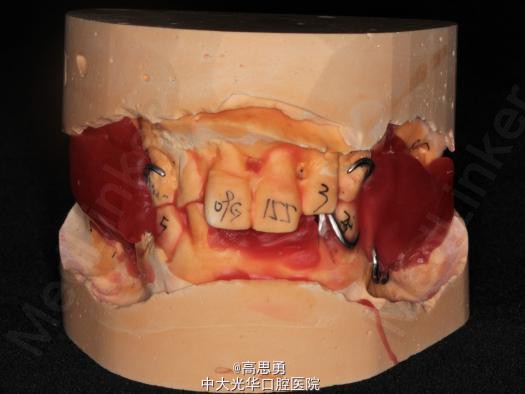

2、研究模型 调拌藻酸盐印模材料于2号成品托盘上取上下颌研究模,灌注石膏模型,研究分析、制定治疗计划,并制作个别托盘。

3、基牙预备 对#13近中、#23远中、#27近中、#34近中、#47近中常规制备支托凹,抛光。

4、工作模型 调拌藻酸盐印模材料于个别托盘上。做一定的边缘整塑,取上下颌研究模,灌注石膏模型。

5、试戴支架 检查支架的就位、固位可,无翘动,调HE,抛光,用蜡堤取颌位关系,上颌架,排牙,比色C4。